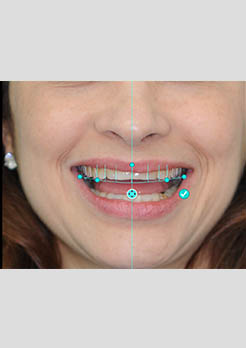

Antes – Planejamento Digital do Tratamento

Planejamento Digital